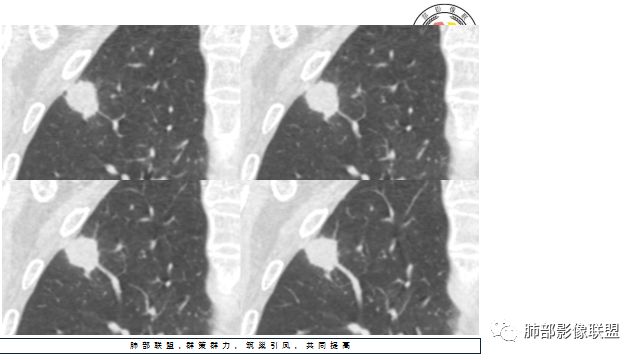

2.右肺尖类圆形结节影,边界清楚,未见明显分叶或深切迹,部分分边缘较平直,可见细长毛刺棘状突起,相邻胸膜增厚,未见胸膜凹陷。后段胸膜下见条索影及微小结节影。

相关血管未见脐凹,有限图像层面未能显示相关支气管情况。

好发于肺尖或尖后段胸膜下的密度不均的结节什么病最常见?结核!

小病灶常常出现空洞的什么病最常见?结核!

空洞内外壁都很清楚的什么病最常见?结核!

周围伴随小结节及条索影的什么病最常见?结核!